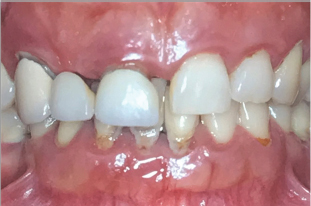

Diabetic patients have shown more severe periodontal disease than healthy control groups, especially when poor glycemic control is present Figure 2 shows a diabetic individual with severe periodontal disease, teeth are longer with increased mobility and migrations, roots are exposed and inflammatory signs can be observed in the gingival (edema, redness and bleeding). We also can see extreme bone destruction around teeth in X-rays from Figure 3 (bone should be 1,5mm below the enamel of the crown). One hypothesis to explain this damage in the periodontal tissues states that advanced glycosylation end products that appear in diabetic patients due to the hyperglycemia make the immune system hyperreactive to dental plaque, increasing destruction of periodontal support [1-3].

Figure 2: Patient 1: Severe periodont it is in a diabetic patient.